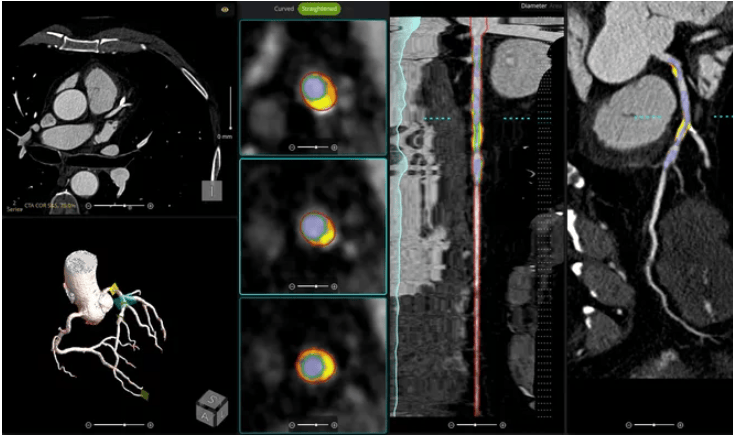

维度网讯,使用人工智能(AI)进行冠状动脉斑块分析已成为心脏病学领域的重要趋势。通过评估冠状动脉CT血管造影(CCTA)图像中的斑块特征,这种非侵入性技术能够详细观察患者冠状动脉状况,避免了传统有创检查的风险。2024年,该技术获得了全新的第一类CPT代码,同时医疗保险覆盖范围得以改进,确保医疗团队的时间得到合理补偿。

越来越多的医疗团队开始采用AI驱动的冠状动脉斑块分析工具来诊断、治疗和管理疑似冠状动脉疾病(CAD)的患者。然而,如何调整现有工作流程以最大化效益,并妥善处理编码与计费问题,成为实施过程中的关键挑战。为此,《心血管业务》与Circle心血管影像公司联合主办了一场免费网络研讨会,专门探讨相关解决方案。